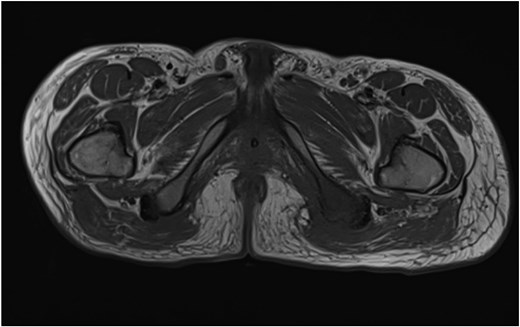

He was admitted to the Plastic and Reconstructive Surgery service for investigation and multidisciplinary management. Initial blood tests demonstrated mild anaemia, mildly elevated white cell count. His C reactive protein was 39. Liver and renal function tests were normal. Magnetic resonance imaging (MRI) demonstrated features of osteomyelitis within the left ischial tuberosity (Fig. 1) and bony involvement extending to the inferior pubic ramus (Fig. 2). Surgical biopsy was performed, with confirmation of osteomyelitis and deep tissue infection. Growth of staphylococcus epidermis and streptococcus anginous was demonstrated in pressure wound and bone chip samples.

Axial MRI image demonstrating loss of normal T1 bone marrow signal is demonstrated involving the left ischial tuberosity. Findings in keeping with osteomyelitis.